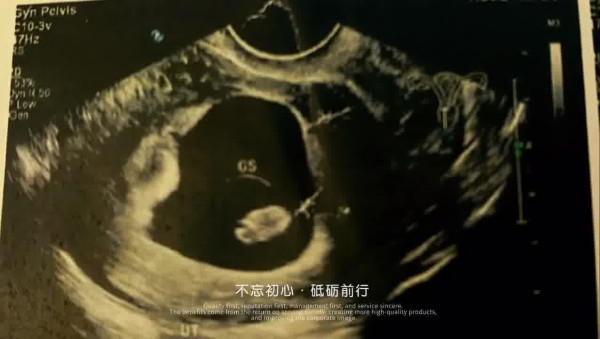

今日,娜娜在社交網分享影片,片中有屯門娜娜懷孕期間的多張相片,又有產子後與老公及兒子合照,留言:「我的天使寶寶終於比預期還要健康的出世了,太可愛了!你要快高長大丫!感謝上天、感謝老公、感謝醫生及醫護人員的貼心照顧、感謝支持我關心我的家人朋友粉絲們!希望大家都能夠健健康康,平平安安,大吉大利接好運!#屯門娜娜 #龍仔 #健康寶寶」

↓↓↓按圖看娜娜懷孕全過程↓↓↓